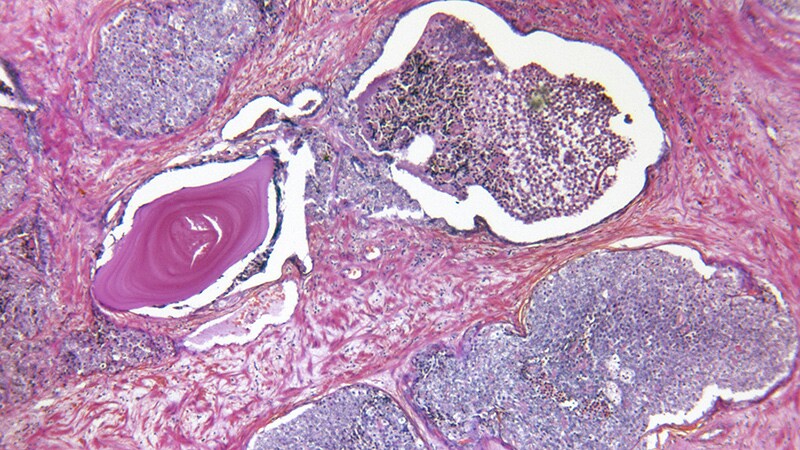

Pathology & Lab Medicine

Hematology-Oncology

Oncology